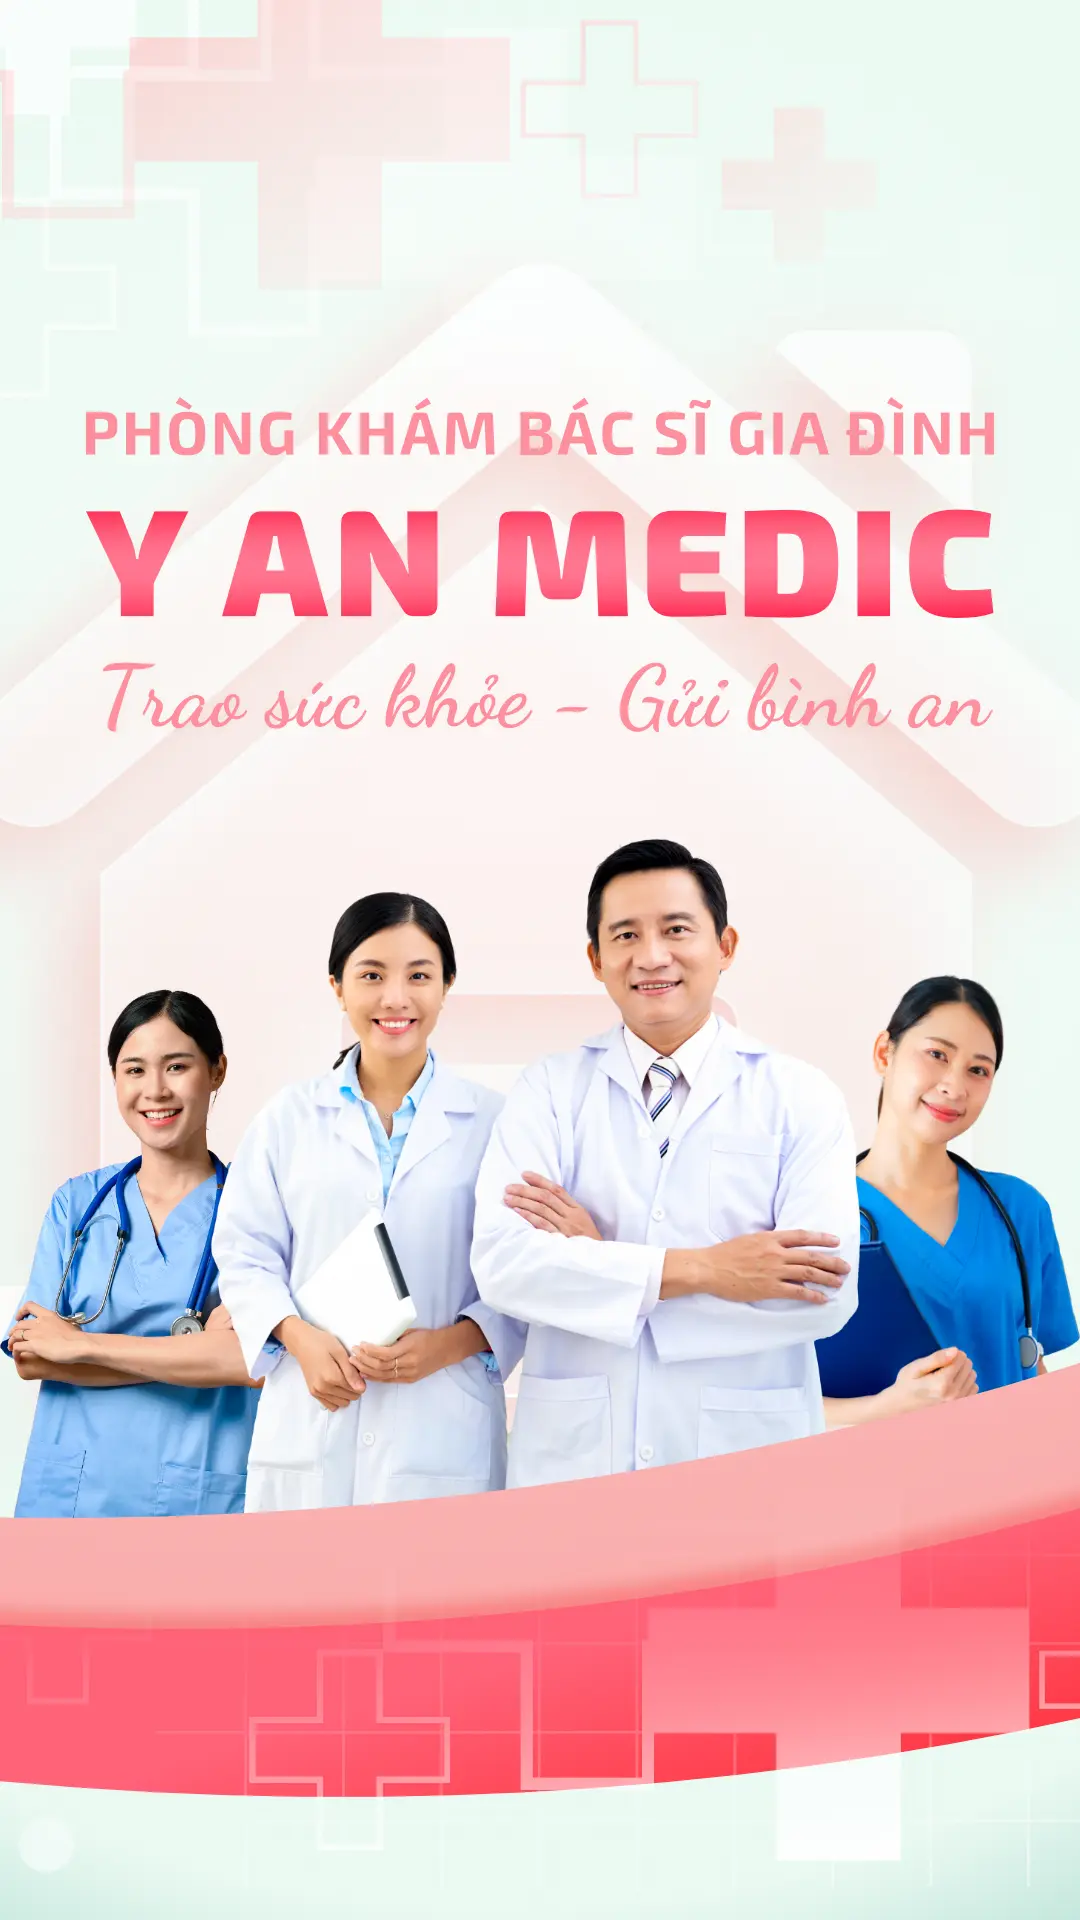

Bác sĩ gia đình điều trị bệnh lý phổ biến, tư vấn phòng bệnh, theo dõi sức khỏe lâu dài và hỗ trợ tâm lý. Mô hình này đề cao mối quan hệ lâu dài giữa bác sĩ và bệnh nhân, giúp nâng cao hiệu quả điều trị và giảm chi phí y tế.

Đặc biệt, Bác sĩ gia đình được phép khám bệnh tại nhà, giúp bệnh nhân thuận tiện trong việc tiếp cận dịch vụ y tế và tiết kiệm thời gian đi lại.

bác sĩ gia đình